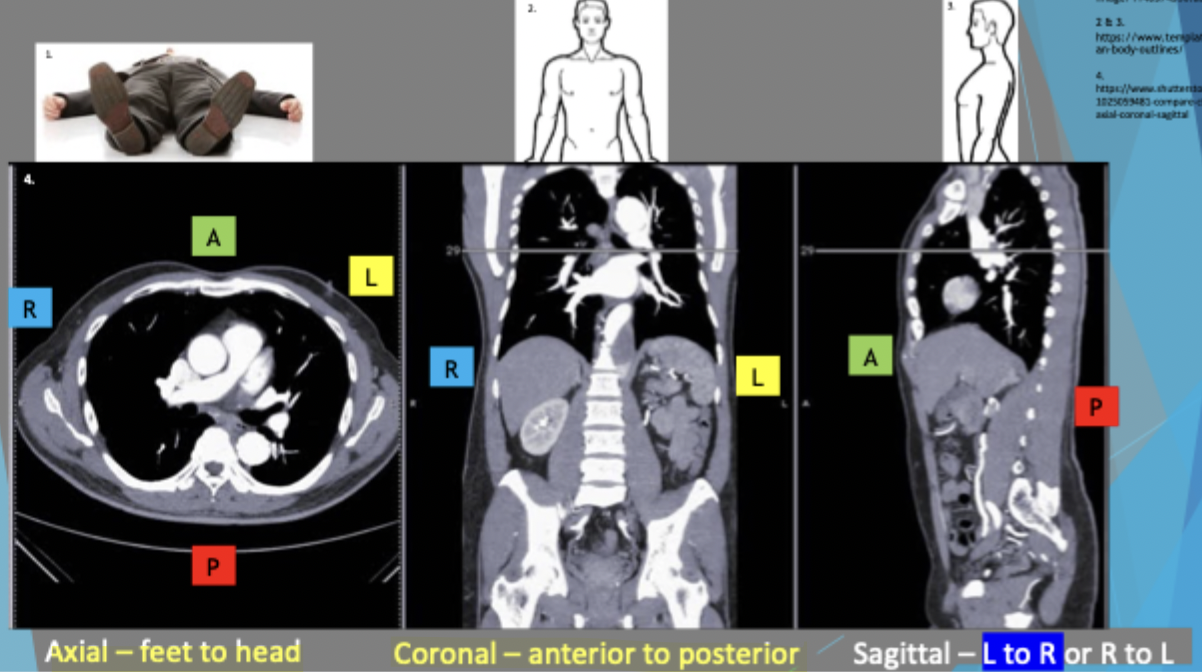

Anatomical slices/sections

Sagittal (median/mid-sagittal, parasagittal): cuts into the right and left side

Coronal/frontal: separates front and back

Transverse/Axial/Horizontal: separates upper and lower part

Viewing and orientation

Axial is looking from feet to head, anterior is superior in the image and posterior is inferior

Coronal: looking at patient face to face and anterior side is separated so you’re looking at posterior side

Sagittal: L to R or R to L. Left to right = seeing right side as left is cut away